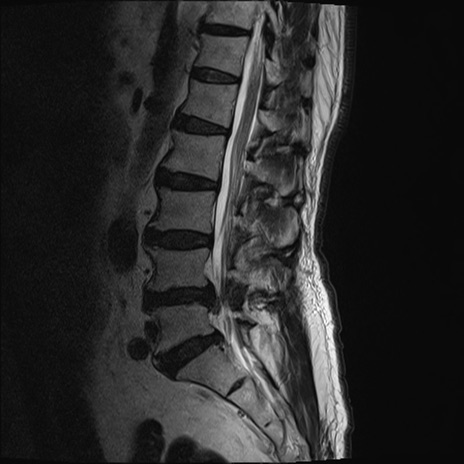

【整形】TIPS症例2 腰椎MRI T2WI(矢状断像)

【症例】70歳代男性

【主訴】左下肢痛

【現病歴】2週間前くらいから腰痛、左下肢痛あり。左臀部から大腿、下腿外側のしびれが常時ある。歩行とともに同部位の痛みあり。

【身体所見】Lasegue70-/60+、Bragard-/±、PTR ±/±、ATR -/-、IP 5/5、TA 5/4、TS 5/5、EHL 右第1足趾なし/3、FHL 5/5、hypersthesia(-)、足背動脈触知良好

異常所見と診断は?